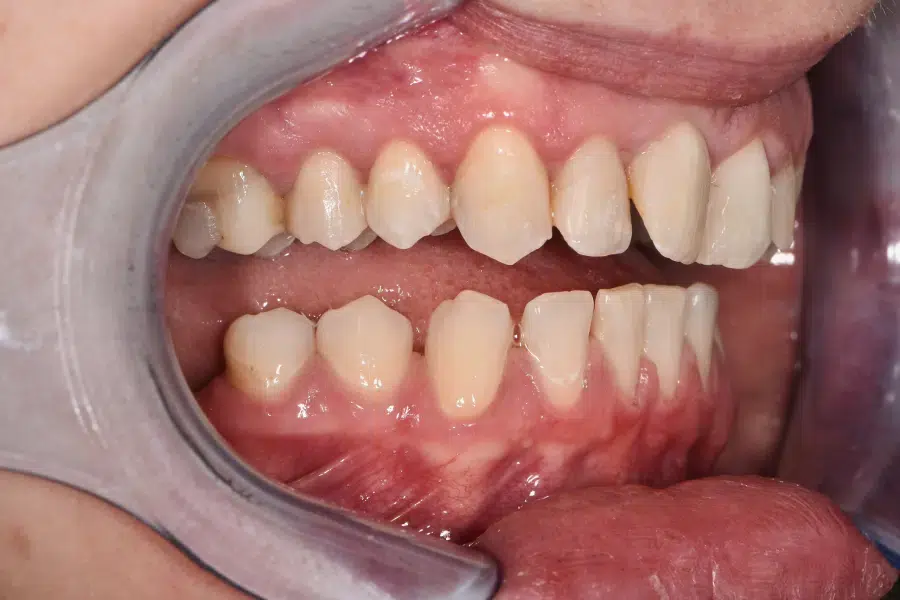

Caz estetică dentară – 4 coroane de zirconiu și ceramică E-Max

Provocarea acestui caz a fost în corectarea dinților laterali mult rotați prin aducerea lor la plan împreună cu incisivii centrali, pacienta refuzând purtarea unui aparat dentar.

Pacientă a beneficiat de corecție gingivala cu laser pentru asimetriile gingivale, tratamente endodontice de canal sub microscop, obturațiile vechi (plombe) schimbate cu materiale de compozit cu particule nanoceramice și 4 coroane de zirconiu ceramică.

Termen de finalizare 2 săptămâni de la amprentarea finală.